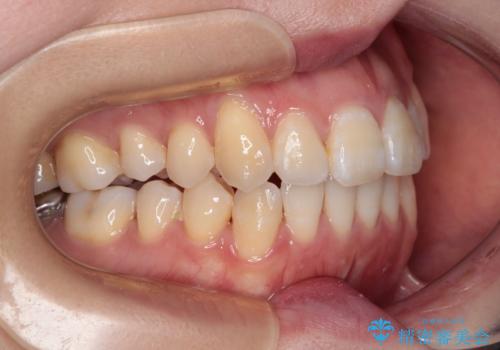

八重歯と開咬の抜歯矯正 ワイヤー装置を併用したインビザライン矯正治療

- 咬み合わない前歯と八重歯などのデコボコを気にして来院された患者様です。

上下前歯の位置を比較すると上顎が前方にあり、デコボコ改善でより上顎が前方に行く可能性があります。

開咬の改善にはインビザラインが有効であり、インビザライン単体での治療を検討しましたが、上顎前突を回避するために上顎左側第一小臼歯抜歯を行うこととしたため、補助装置とワイヤー矯正を併用した上で、インビザラインによる矯正治療を行うこととしました。

インビザライン矯正治療では、臼歯の圧下による前歯部の早期接触が大きな問題となっています。開咬では、その臼歯圧下を逆手にとって前歯部の非接触を改善させることができます。